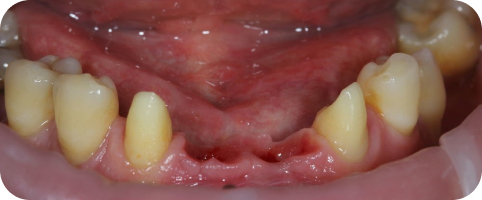

У мужа была очень непростая ситуация: неправильный рост зубов и запущенный гингивит. Хотелось поблагодарить персонал за вежливость, понимание и хорошее отношение. Большое спасибо врачу Щегловой Ирине Вениаминовне за лечение и спасённые зубы!

Хочу выразить огромную благодарность врачам и всему персоналу клиники Зубной доктор! Низкий поклон Журавлеву А.В., Осадчему Е.А, Гапоненко А.Д специалистам, проделавшим большую, без преувеличения ювелирную работу и вернувшим мне улыбку! С детства зубы были большой проблемой, а к 55 годам стали буквально катастрофой! Теперь же могу смело смеяться, без проблем есть и это очень здорово! Всем своим знакомым рекомендую данную клинику и врачей! Отличные профессионалы, чуткие и отзывчивые люди. Моего словарного запаса не хватает чтобы выразить восторг, который вызывает проделанная ими работа! Желаю успеха и процветания клинике!